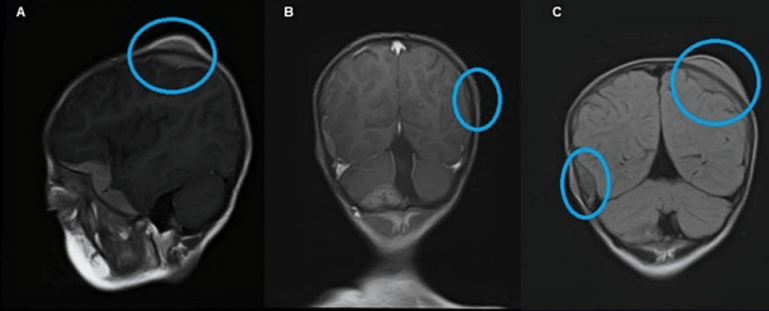

Magnetic resonance imaging (MRI) of the brain and orbit showed an intraocular retro-globular mass with retinal detachment and orbital hemorrhage. There were multifocal scalp-based lesions with an enhancing extradural soft tissue component along the left greater wing of the sphenoid, bi-frontal, and left parietal regions, causing bulges and mild leptomeningeal enhancement (Figure 2 [Fig. 2] and Figure 3 [Fig. 3]).

Figure 3: MRI showing multifocal scalp-based lesions with enhancing extradural soft tissue component seen along the left greater wing of sphenoid, bifrontal, and left parietal region producing bulge and mild leptomeningeal enhancement. Sagittal MRI (A), post-gadolinium coronal MRI (B), and FLAIR (C) show multifocal scalp-based lesions with enhancing extradural soft tissue components seen along the left greater wing of sphenoid, left high parietal, and left occipital region.